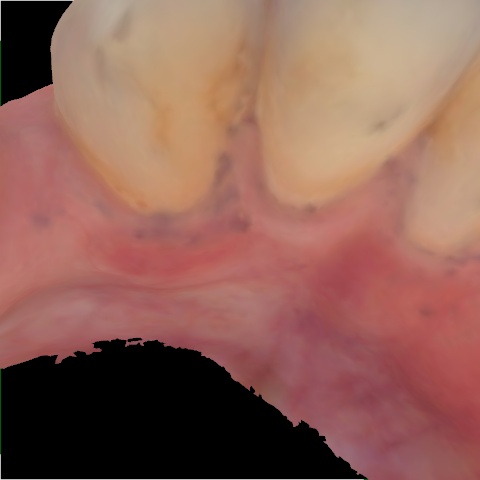

Image 66 / 400

NHD20794

Annotated as "Bad"

Original Image Rendering Image